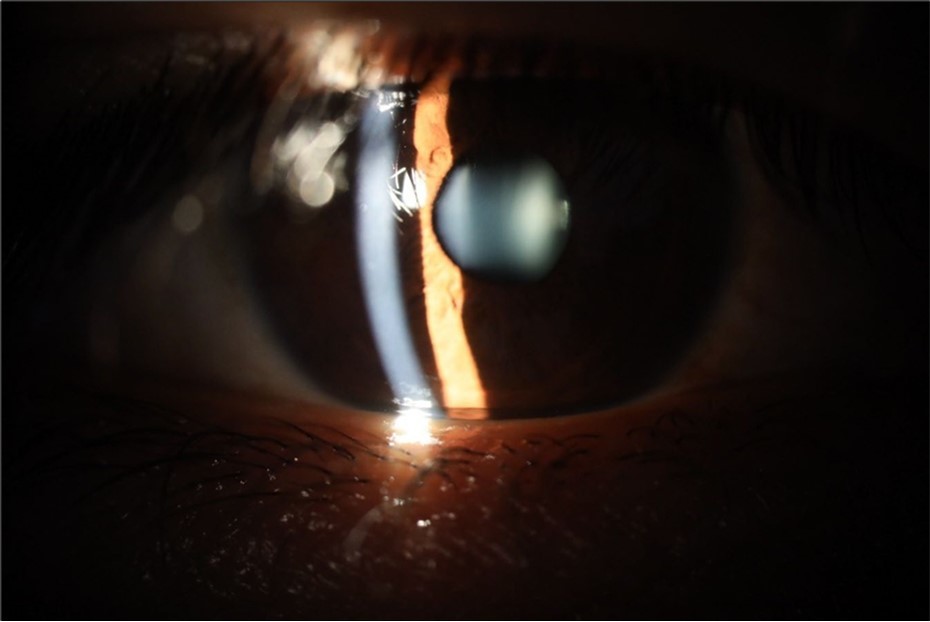

Figure 5.The slit-lamp photograph shows the anterior segment, relatively unscathed, in terms of transparent media (Cornea, crystalline and vitreous).

Figure 15.The photograph shows better specular reflection, compared to the first day of the exam.

Figure 16.The anterior segment of the right eye shows the vitreous with greater transparency. The cornea and lens, as well as the anterior chamber, are in good condition.